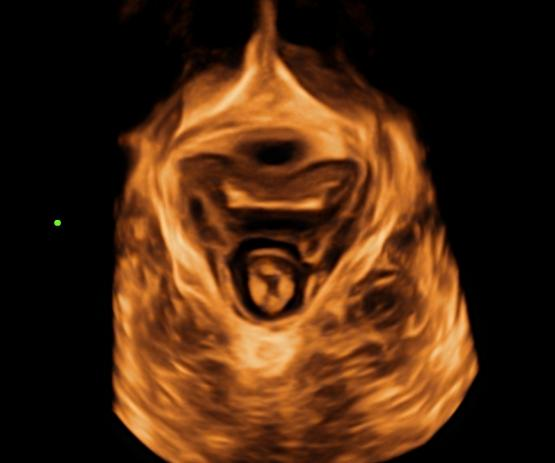

盆底超声是将超声探头放在患者会阴部、阴道或者直肠内获取超声图像的一种检查。它可以清楚显示直肠壁的分层和肛门括约肌,同时还能清楚显示前盆腔的尿道、中盆腔的阴道及后盆的耻骨直肠肌、坐骨直肠间隙的正常解剖形态,为后续超声诊断盆底疾病奠定了基础。目前,盆底超声因其优点明确也开始逐步应用于评估便秘相关的后盆腔形态和功能。

阴道与直肠二维超声图 会阴部三维超声图